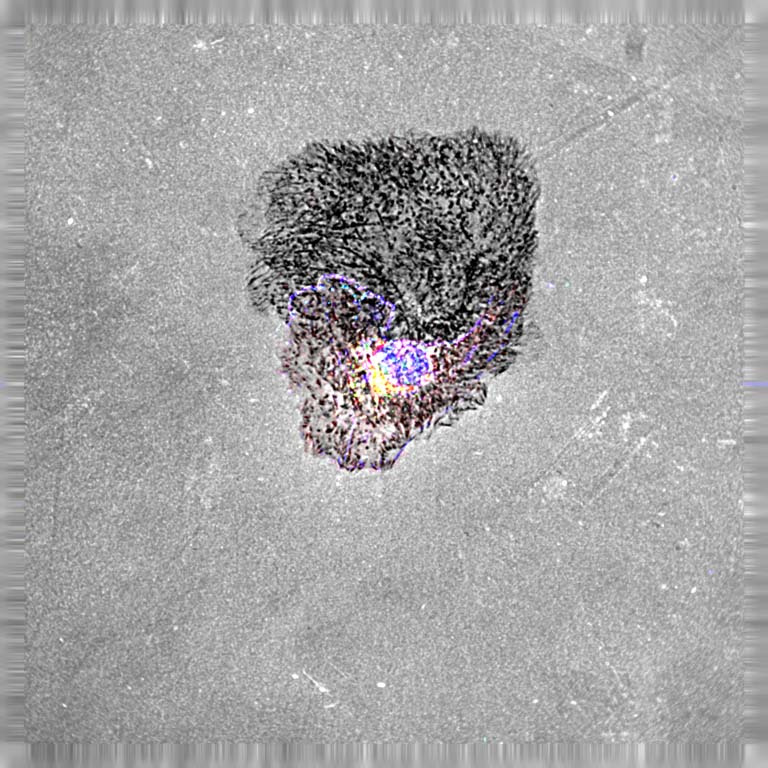

This image shows how cell invasive phenotype is affected under low pH conditions. Low extracellular pH is a hallmark of tumor microenvironment. Cells within the tumor microenvironment are exposed to acidic regions, which has been shown to promote growth and metastasis. Such conditions while harsh on normal cells promotes invasion and migration on cancer cells therefor an advantage for tumor cell invasion. In this image, a breast cancer cell becomes highly aggressive and invades the substrates (black puncta) when exposed to stress conditions.